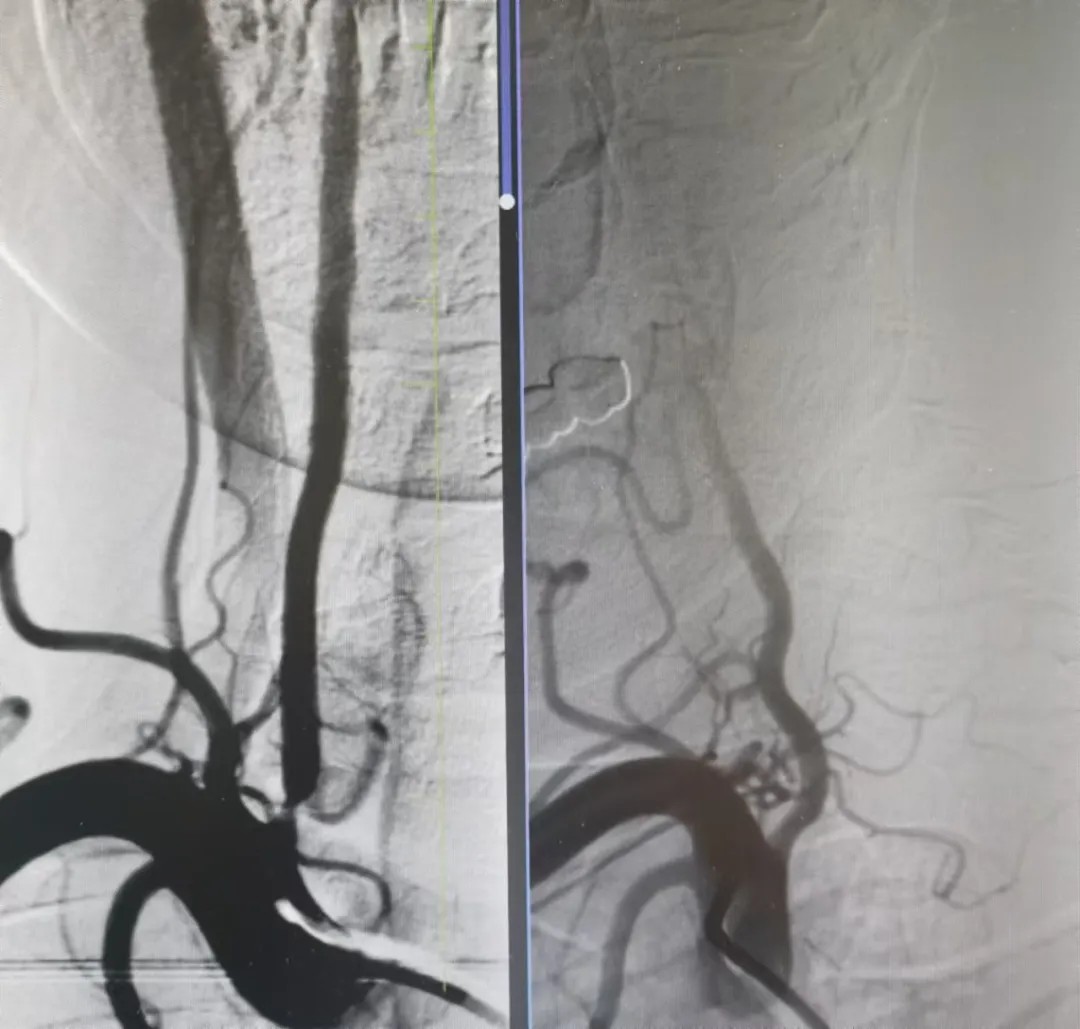

家屬同意后,神經(jīng)介入科團(tuán)隊迅速給予行腦血管造影,結(jié)果提示:右側(cè)椎動脈重度狹窄。朱洪波副主任表示:該處一旦發(fā)生循環(huán)梗死,輕則癱瘓在床、重則昏迷不醒甚至危及生命,建議盡快對重度狹窄血管積極處理。家屬對患者病情及治療方案詳細(xì)了解后,決定接受介入手術(shù)治療。

手術(shù)在局麻下施行,通過經(jīng)橈動脈入路,予以行右側(cè)椎動脈起始處重度狹窄球囊擴張術(shù),經(jīng)股動脈穿刺,微導(dǎo)絲送入球囊至病變狹窄部位進(jìn)行擴張,擴張后造影提示狹窄部位擴張滿意,基底動脈血流明顯改善,手術(shù)順利結(jié)束。術(shù)后陳大叔上述癥狀完全恢復(fù),大叔妻子感激地說:“感謝國文醫(yī)院的積極救治,來的時候老陳都暈的無法走路,現(xiàn)在都能自己行走了,太感謝了?!?/p>